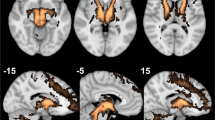

Utilizing all available pre-treatment samples for each of the modality of biomarkers (fMRI [brain]: N = 278; EEG [brain]: N = 275; immune/metabolic [blood]: N = 212), top five pre-treatment features associated with baseline MDD were derived using the PPS feature selection algorithm (all features and their predictive power scores are listed in Supplementary Table 3). The top five fMRI features represented connectivity between various brain regions including the anterior cingulate, striatum, calcarine, and more. The EEG features represented alpha band connectivity across different regions. The top five EEG and fMRI network connectivity regions are visualized in Supplementary Fig. 2. The top five blood features were chemokine ligand-1, interleukin-4, interleukin-8, chemokine ligand-26, and chemokine ligand-13. As the final features selected had no missingness across participants, imputation was not needed. These 15 biological pre-treatment features with the addition of 3 demographic features (age, sex, and race) yielded 18 features for predicting remission of MDD at week 16 of treatment.